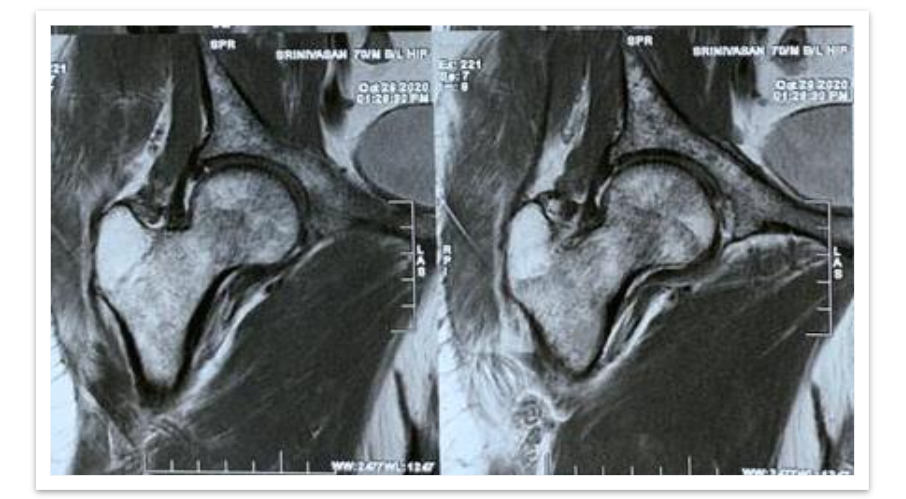

MRI Hip (left) revealed undisplaced fracture in the femoral neck, multiple focal altered signal intensity lesions in the proximal femur and pelvic bone. HRCT chest showed expansile lytic lesions with bone erosions in the posterolateral aspect of left 6th rib; Multiple target lytic lesions in cervical and thoracic vertebrae. Impression was given as metastasis can be considered.

All of the blood values were unremarkable. Total WBC count was 5360/cu.mm, ESR was 75mm, Hb was 11.2gm/dl, RBC was 3.39 million, and Platelets were 1.85 lakh. Thyroid function tests, serum amylase, lipase, clotting time, and bleeding time were all normal. Urine routine showed protein 2+. Serum calcium was 10 mg/dl, serum phosphorus was 3.7 mg/dl, and serum alkaline phosphatase was 87 IU/L. Following all of the tests, the clinical diagnosis was reported as a pathological fracture of the left neck of the femur with several lytic lesions in the B/L proximal femur, pelvic bone, thoracic lumbar vertebras and 6th rib without shortening. A Dynamic Hip Screw procedure was performed on the left hip, and the tissue sample was sent for histological evaluation.